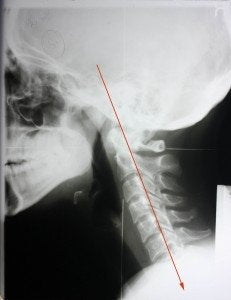

Military Neck is when there is minimal cervical curvature in the neck. The spine is straight up and down. It should have a natural "c" curve in it.